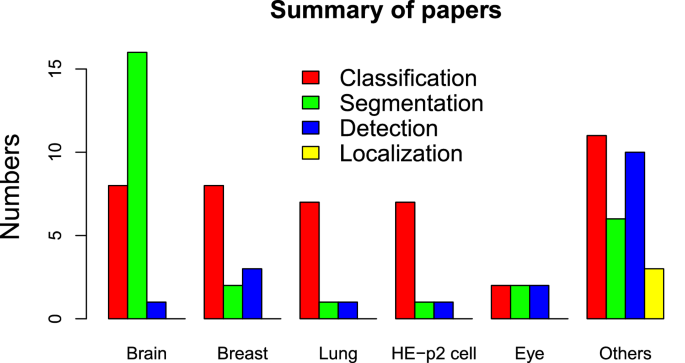

The literature reviewed in this paper underscores that researchers have focused their attention on the use of CNN to overcome many challenges in medical image understanding. Many have accomplished the task successfully. The CNN methods discussed in this paper have been found to either outperform or compliment the existing traditional and ML approaches in terms of accuracy, sensitivity, AUC, DSC, time taken etc. However, their performance is often not the best due to a few factors. A snapshot summary of the quantum of research articles surveyed in this article is presented in the Fig. 2 .

Bar chart summarizing the number of papers surveyed